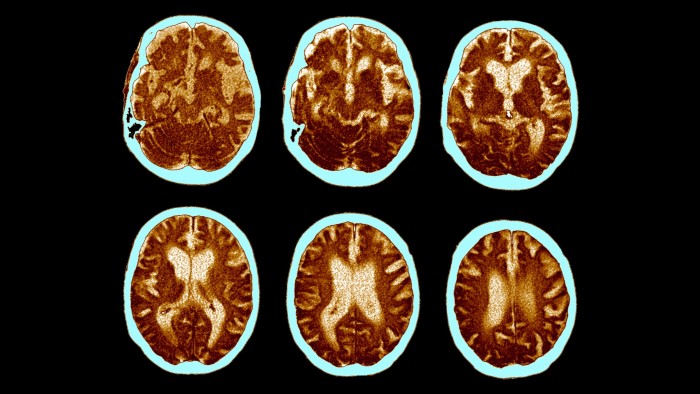

However, the Novo trials focus on a different stage of the disease: all of the participants already show a build-up of amyloid on brain scans.

If GLP-1s work only on those who do not already have this build-up, instead preventing Alzheimer’s before it has started, the trial will look like a failure.